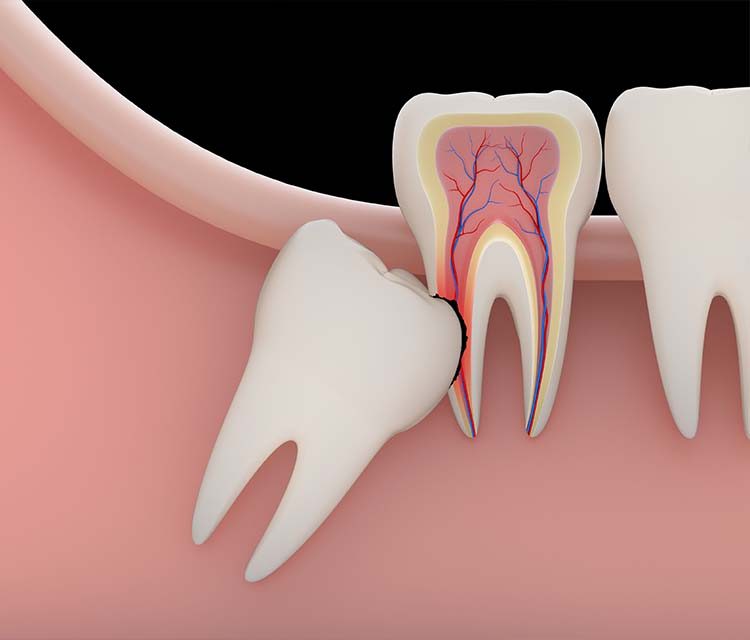

Gömülü dişler, sadece çene yapısı ve genetik faktörlerle sınırlı kalmaz, aynı zamanda dişlerin çıkma sürecindeki yönlendirme eksikliklerinden de kaynaklanabilir. Dişler çıkarken yanlış bir açıyla büyüyebilir ve bu da onların diğer dişlerin arkasında veya diş eti altında kalmasına neden olabilir. Bebeklik döneminde dişlerin çıkma sırasındaki problemler, gelecekte gömülü dişlerin oluşmasına zemin hazırlayabilir. Bu nedenle, erken yaşlarda düzenli diş kontrolleri yapmak, ileride oluşabilecek diş sorunlarının önlenmesi açısından önemlidir.

Cerrahi müdahale genellikle lokal anestezi altında gerçekleştirilir ve diş eti kesilerek dişin çıkarılması işlemidir. Bu süreçte dişin çevresindeki kemik dokusu da çıkarılabilir. Ameliyat sonrası iyileşme süreci genellikle birkaç gün ile birkaç hafta arasında değişir ve bu dönemde hastanın ağız hijyenine dikkat etmesi, hekimin önerdiği ilaçları kullanması önemlidir. Ayrıca, cerrahi sonrası oluşabilecek ağrı ve şişlik gibi belirtileri hafifletmek için soğuk kompres uygulamaları önerilir.